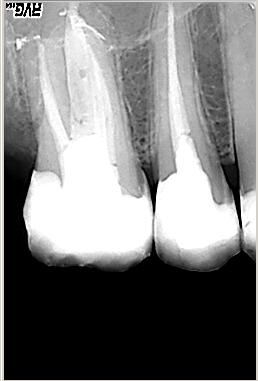

WF Kontrolle

WF Kontrolle im Februar 2003. Dichte dreidimensionale Wurzelfüllung in vertikaler Kondensation erwärmter Guttapercha mit System B und Obtura 2

Langzeitkontrolle

Langzeitkontrolle 11 Monate nach WF; im Januar 2004 wurde eine Goldteilkrone eingegliedert